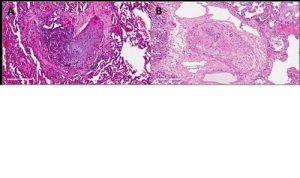

Mehr erfahren zu: "Überraschende Ergebnisse zur Sterblichkeit an Thrombosen und Lungenembolien" Überraschende Ergebnisse zur Sterblichkeit an Thrombosen und Lungenembolien Das Centrum für Thrombose und Hämostase (CTH) der Universitätsmedizin Mainz hat Studienergebnisse in „The Lancet Respiratory Medicine“ veröffentlicht: In Nordamerika ist für den Zeitraum 2000 bis 2017 eine sinkende Todesrate […]